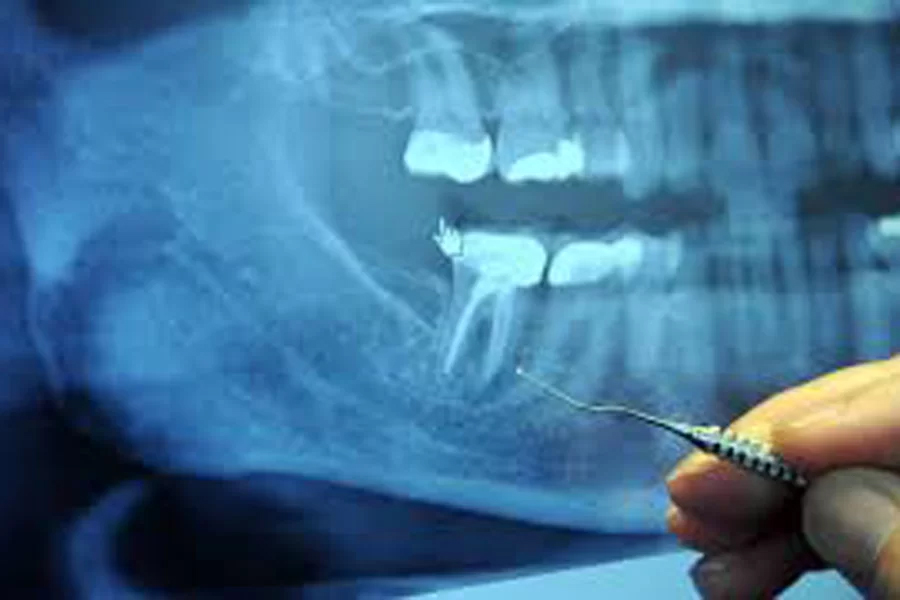

妊婦さんに配慮したレントゲン検査

「妊娠中のレントゲンは赤ちゃんに影響があるのでは?」と心配される方も多いですが、歯科用レントゲンは極めて少量の被ばく線量であり、撮影部位もお腹から離れています。

当院では、さらに安全性を高めるために、下記のような対策を徹底しています。

デジタルレントゲン(被ばく量が従来の1/10)

鉛入り防護エプロンの着用

必要最低限の撮影範囲に限定